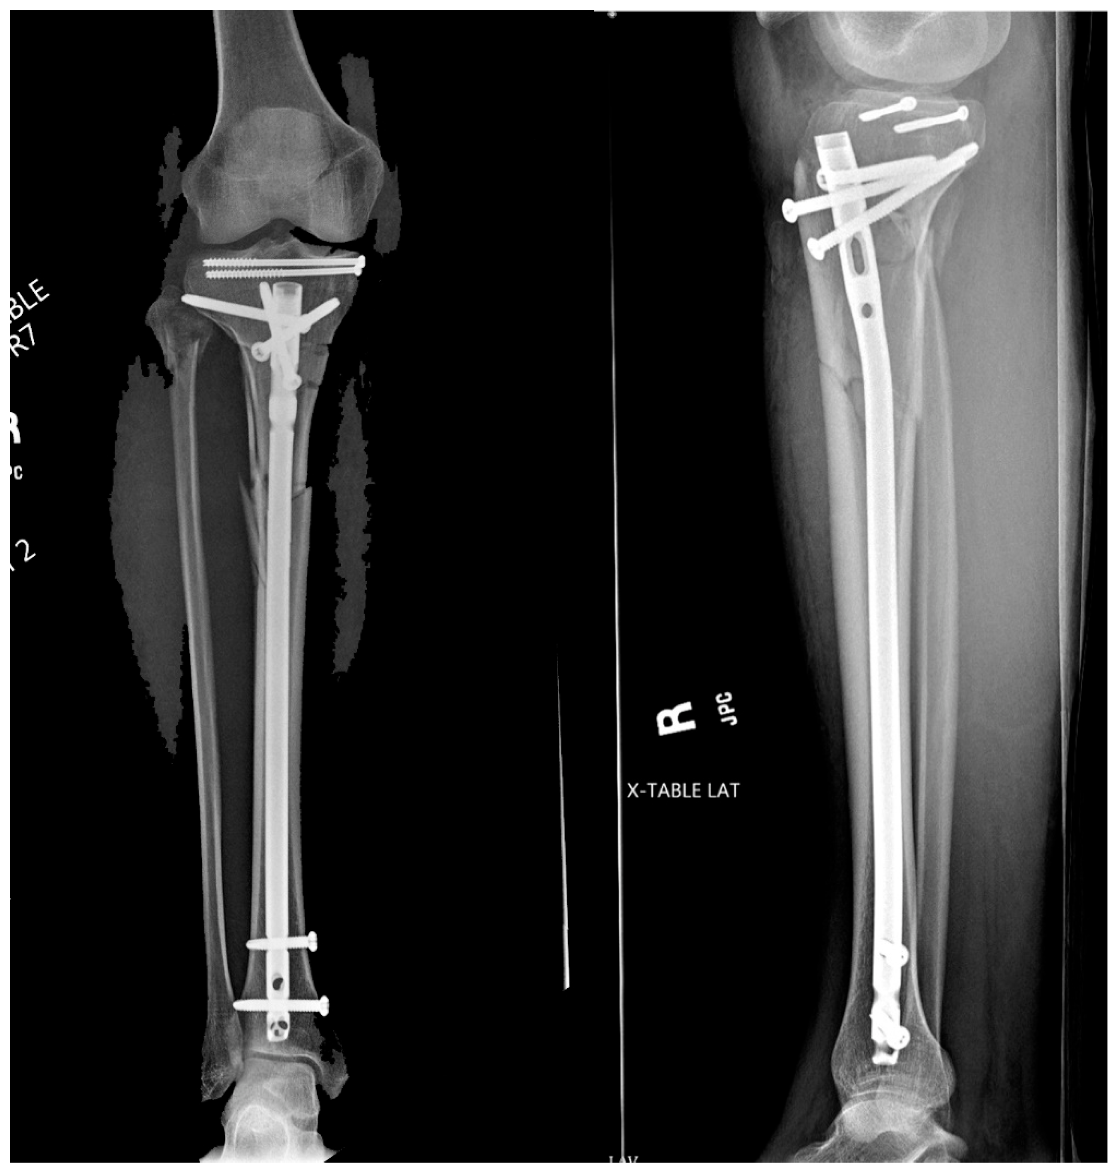

An optimal start site is necessary for a successful surgery, especially when dealing with proximal third metaphyseal fractures (Figure 6). If a start site is close but not perfect, many of the implant systems allow for the insertion of a multi-hole cannula that rotates to make small adjustments in whichever plane necessary, as is being used in Figure 5. It is common knowledge that a medial start site leads to valgus, a lateral start site leads to varus, and a posterior-directed guidewire leads to procurvatum. Although an upward force on the cannula allows for the appropriate start point on the articular margin, the opposite is helpful when using the opening reamer to obtain an entry pathway in line with the sagittal axis of the tibia. If a tight patellofemoral joint is encountered where the cannula is obstructing an accurate start point, the guidewire can be safely inserted without the cannula, and then, the cannula inserted over the top of the wire once positioned. Once the ideal start site is obtained, if the trajectory is not perfect, the wire can first be advanced partially. Next, let the wire be consumed by the opening reamer to allow the reamer to make the adjustments for improved trajectory. The second necessity of treatment of fractures with intramedullary devices is that fracture reduction precedes reaming and nail insertion. Although isthmic fractures reduce well with nail insertion, the authors believe that regardless of fracture location, the fracture should be reduced prior to reaming and nail insertion. This can be achieved with external manipulation, traveling traction, percutaneous clamp application, or formal open reduction with or without plate and screw application. Once the surgery is complete, the authors generously irrigate the joint to remove any reaming debris that may cause post-operative irritation (Figure 7). The quadriceps tendon is closed with a heavy suture, and the skin closed in a standard layered fashion.

Figure 6. Pre-operative injury films.